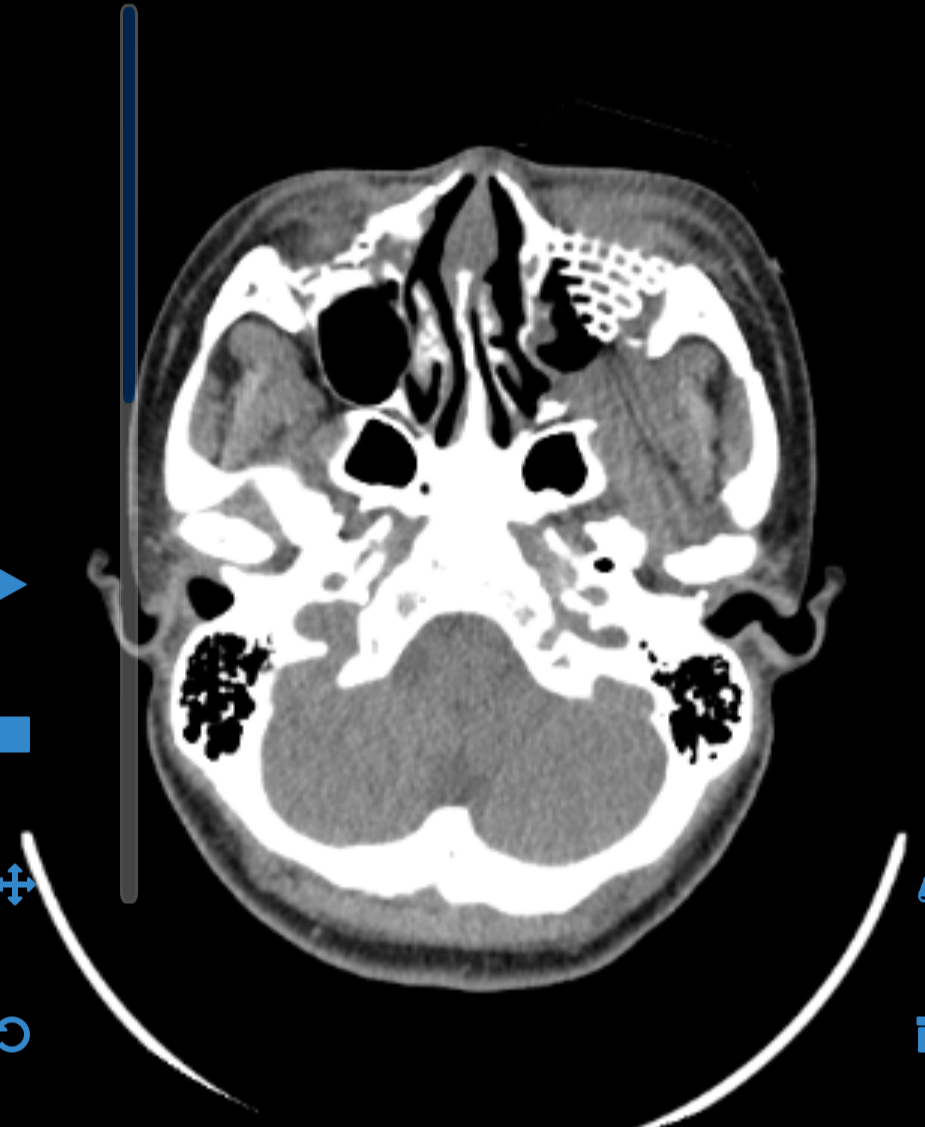

조각조각 나서 일부는 사라져 버린 내 얼굴 뼈. 안구 주변의 뼈들이 부서진 탓에, 그리고 코와 연결되는 점막 장벽들이 무너진 탓에, 내 좌측 얼굴과 코는 외부에서 유입되는 균을 막을 재간이 없다. 30대의 나는 정맥 항생제의 도움으로 한 차례의 위기를 잘 넘어갔지만, 40대, 50대, 60대, 70대의 나는 과연 그럴 수 있을까.

그 말은, 내가 앞으로 견디고 싸워야 할 대상이, 남은 한쪽 눈으로 보게 될 좁은 시야가 아닌, 언제 어디서 들이 닥칠지 모르는 세균들과의 전쟁이라는 뜻이다. 한시도 마음을 놓지 못하고 잔뜩 긴장해야 생존할 수 있는 삶. 감염 징후에 촉각을 세우고 너무 늦기 전에 알아채야 지킬 수 있는 삶, 앞으로 나에게는 안심하고 마음을 내려놓을 여유는 허용될 수 없는 것이다.